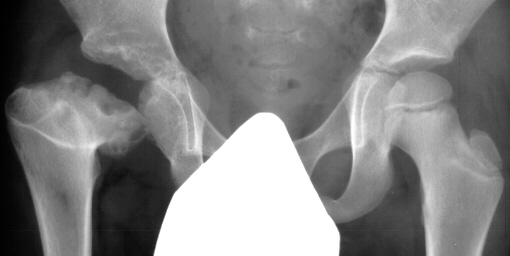

- Post Operative Day 18: R hip Xray: subluxation of R hip, possible metaphyseal

lucency consistent with osteomyelitis. Taken to OR for repeat I & D

of R hip via posterior approach with Penrose drains and hip spica cast

(15cc seropurulent fluid drained). Antibiotics changed to Oxacillin 225mg

IV q4.

- 2 month Office Follow Up: Rt hip Xray: progressive destruction of capital

femoral epiphysis, cystic changes in metaphysis consistent with AVN.

- Age 6: Valgus osteotomy for subluxation and 2cm leg length inequality.

- Age 15: Valgus osteotomy for hip incongruity.

- Age 20: Hip arthroscopy. Hip fusion recommended.

This case is an example of untreated septic arthritis which caused avascular

necrosis of the proximal femur. The primary cause of this is undrained

septic hip. Repeated aspiration is not adequect treatment of a septic hip.